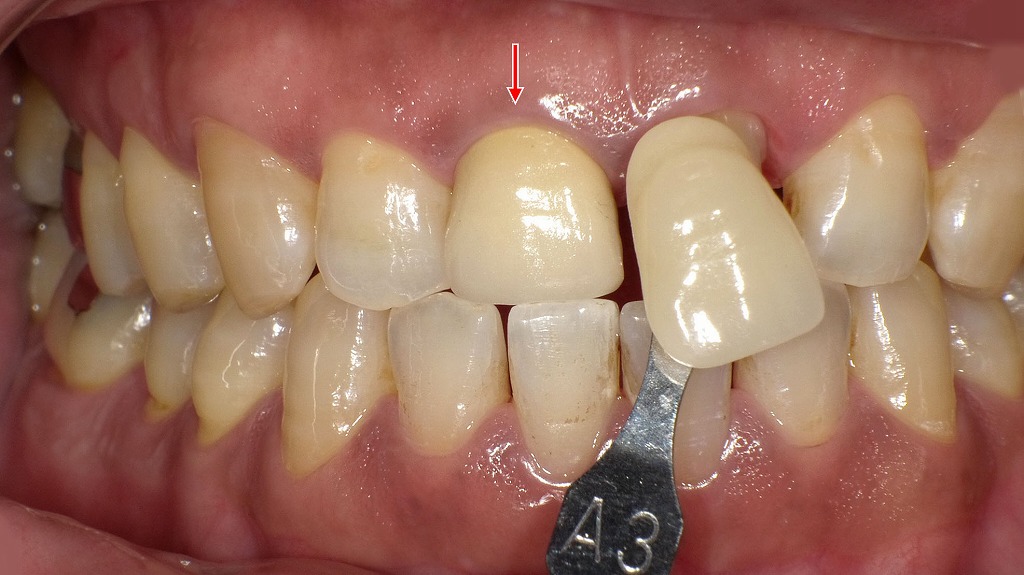

上顎左右1番に装着された硬質レジン前装冠です。長期使用により、前装部の黄ばみ(変色)と表面の摩耗が認められます。硬質レジンは保険適用で広く用いられますが、時間の経過とともに着色しやすく、艶が失われるという特性があります。審美性の低下や周囲歯との色調不調和が生じた場合は、再製作やセラミック冠への変更を検討することがあります。

右上1番にはオールセラミッククラウンを装着し、自然な透明感と周囲歯との調和を回復しています。一方、左上1番は修復前のシェードテイキングを行っている段階で、隣在歯や対合歯の色調を確認しながら、最適な色味を選択しています。左右の色調差を最小限に抑えるため、精密なシェード選択が審美修復の仕上がりを左右する重要な工程となります。